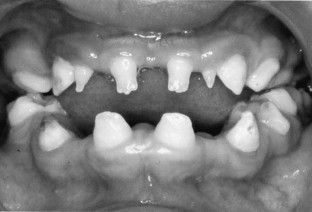

A 3-week-old boy was diagnosed with congenital osteopetrosis. He underwent a bone marrow transplant at 6 weeks of age. At 3 years of age the primary teeth had all erupted, but the canines and the first molars totally lacked root development. The teeth were smaller in size and had evidence of both enamel hypomineralization and hypoplasia. In the permanent dentition, multiple missing teeth were found. The incisors were conical and the mandibular laterals were extremely small. All permanent teeth had normal eruption. This case shows that dental development and eruption of teeth can be reconstituted in a child with congenital osteopetrosis. Bone marrow transplantation induces normalization of osteoclast function, which is a prerequisite for normal dental development and eruption of teeth.